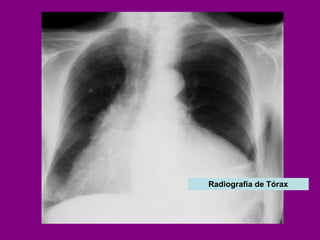

DERRAME PERICARDICO

Aumento de tamaño de la silueta cardíaca  en presencia de derrame pericárdico importante  ( > 250 ml), con forma de «cantimplora».   Radiografía de Tórax

Radiografía de Tórax